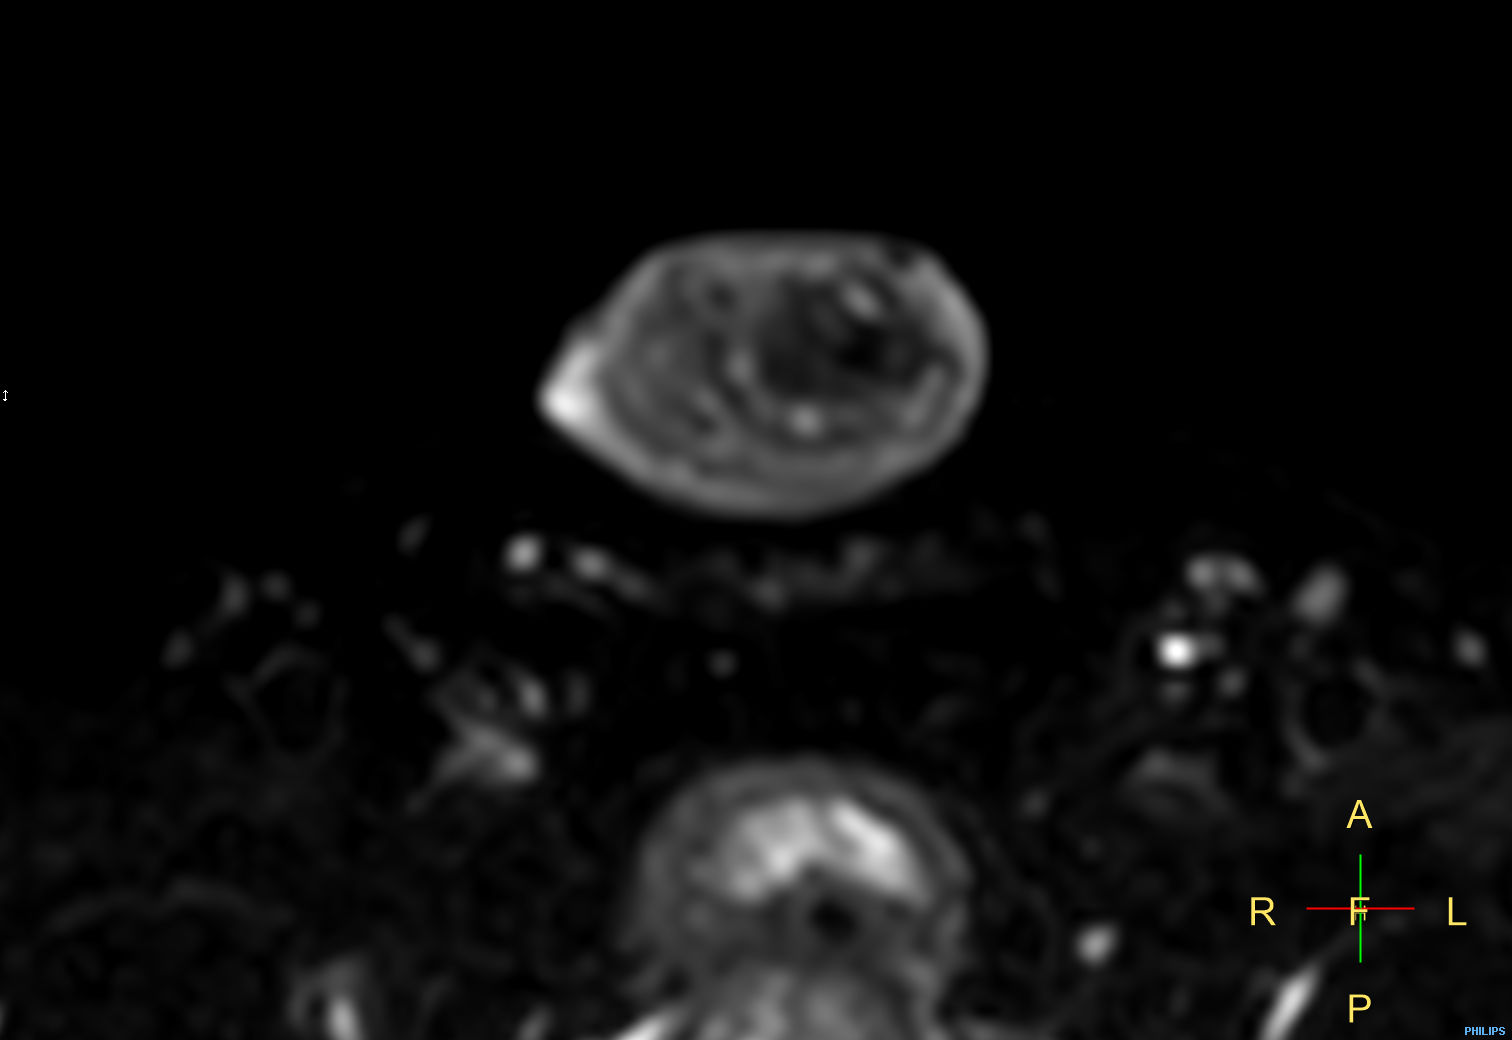

Patient with a penile carcinoma. ExamCard includes Compressed SENSE to shorten exam time, diffusion to achieve high contrast between background and lesions, and MultiVane XD for motion-free imaging in short scan time.

Diffusion (b100)

Diffusion (b1000)

Diffusion (ADC)